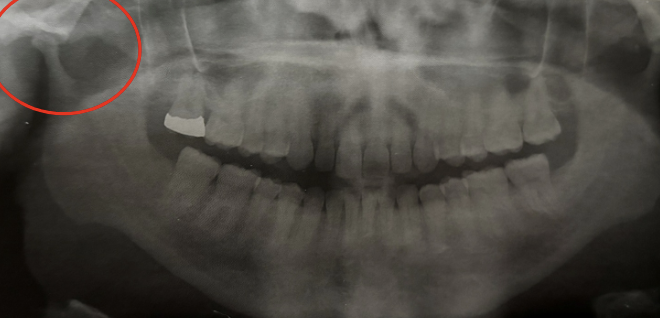

what is shown in the red circle

an artifact

how would you describe this radiographic lesion?

a multilocular radiolucent lesion